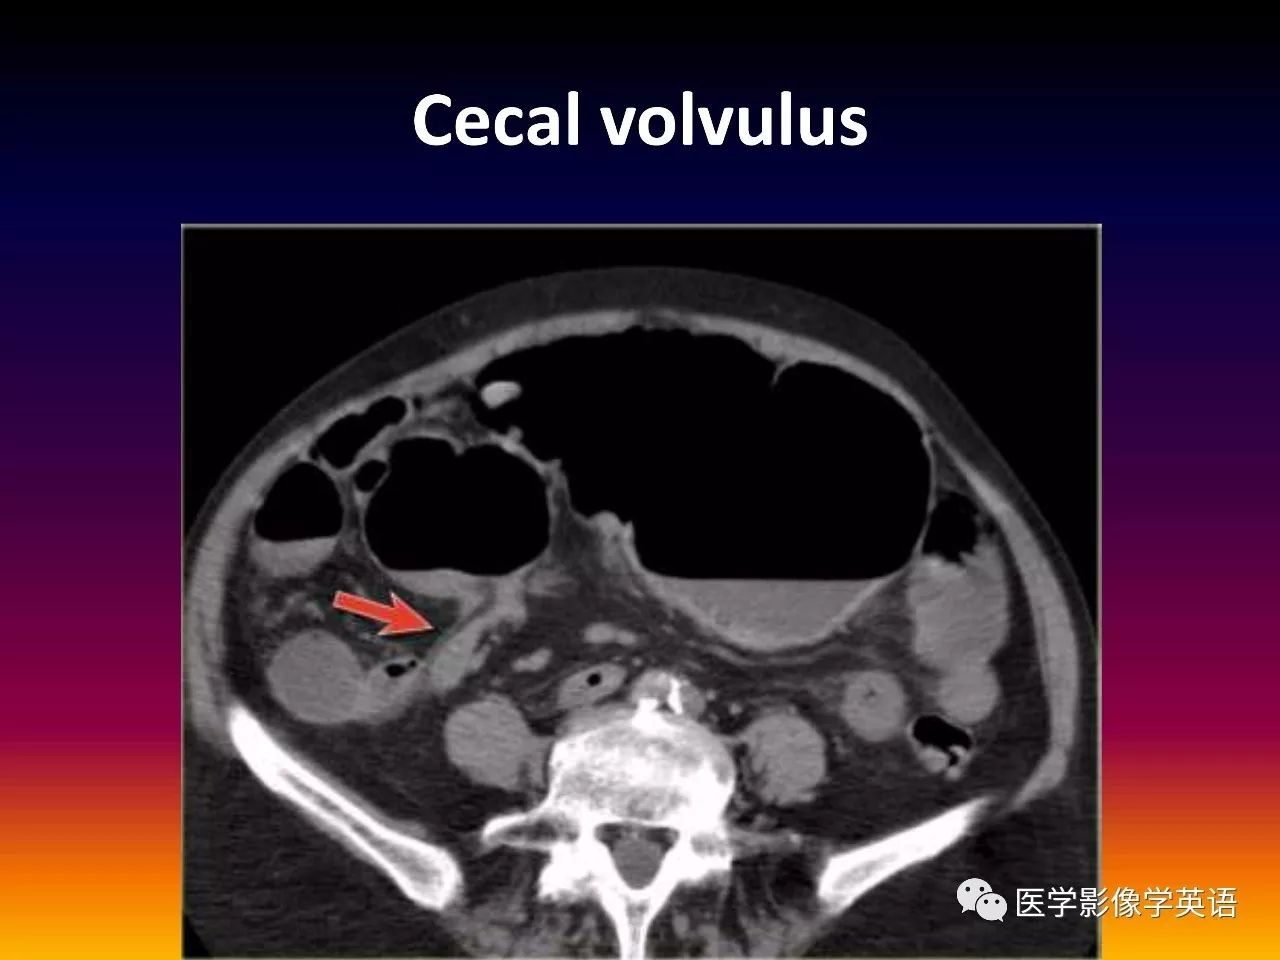

30. Cecal volvulus SMA SMV Beak sign

93. Cecal volvulus

94. Cecal volvulus

95. Cecal volvulus

96. Cecal volvulus

97. Cecal volvulus

98. Cecal volvulus

99. Cecal volvulus

100. Cecal volvulus